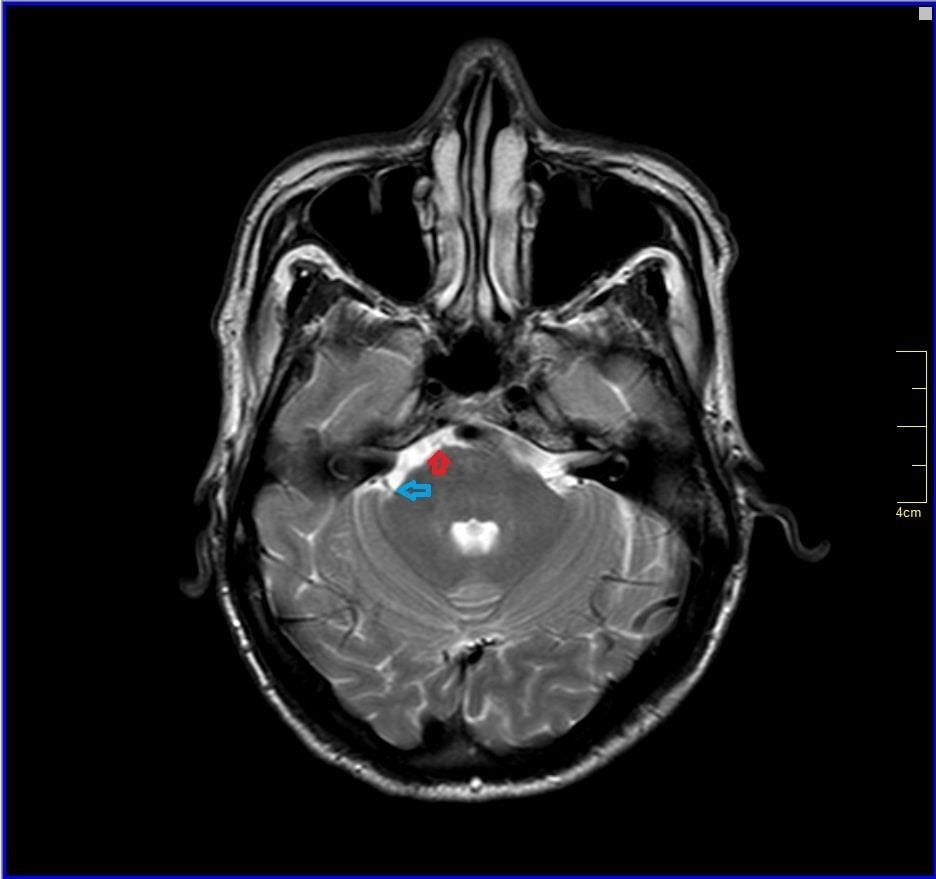

All other blood investigations including thyroid function tests and autoimmune screening were within normal limits. Plain computed tomography (CT) brain was done and revealed well-defined hypodensities seen in right lentiform nucleus chronic infarct.1 Otherwise, no intracranial haemorrhage and no acute ischemic infarcts seen at other areas. Brain magnetic resonance angiography (MRA) was ordered and it showed impingement of V4 vertebral artery to anterior lower pons near midline which is the exit of the left abducens nerve from the pons and also trigeminal nerve (blue arrow) and right abducens nerve (Figure 1-3) No abnormal signals were seen in brainstem. After ruling out other aetiologies of sixth cranial nerve, diagnosis of isolated sixth cranial nerve palsy was made.

Figure 2 Brain magnetic resonance angiography (MRA) showing impingement of V4 vertebral artery (red arrow) to anterior lower pons near midline which is the exit of the left abducens nerve from the pons.